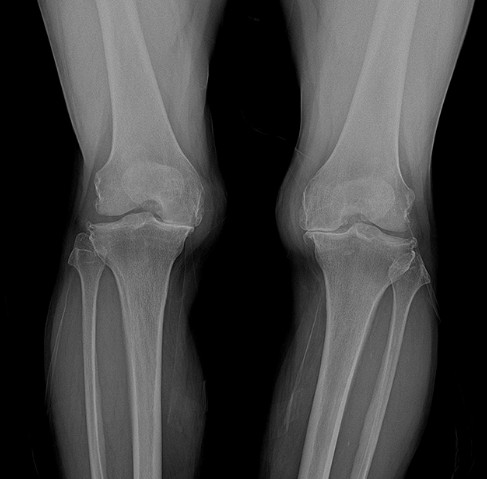

퇴행성 관절염은 관절을 보호하는 연골이 점진적으로 손상되거나 퇴화하면서 관절을 구성하는 뼈와 인대에 손상이 발생해 통증과 염증이 생기는 질환입니다. 이 질환은 주로 60~65세 이상의 노인 중 약 80%가 경험하는 흔한 무릎 질환으로, 최근에는 생활습관과 비만 등 여러 원인으로 인해 젊은 층에서도 빈번히 발생하고 있습니다. 퇴행성 관절염에 걸리면 연골의 분해로 인해 생성되는 염증 물질이 통증을 유발하며, 이는 연골 파괴를 가속화하여 악순환을 초래합니다. 또한 연골이 손상되면서 관절 간격이 좁아지고, 다리가 휘어지는 내반 변형이 생기게 되어 겉으로도 다리가 휘어 보이는 오다리 현상이 나타날 수 있습니다.